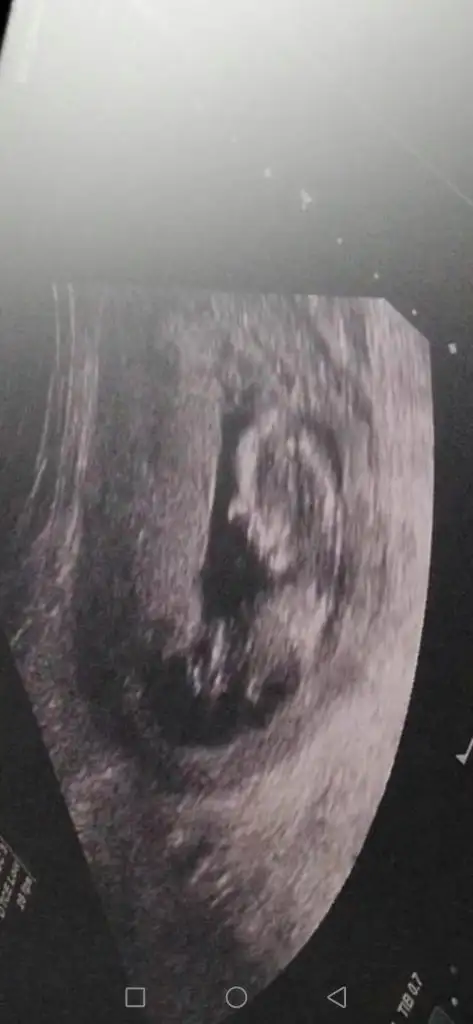

Başka usg varsa paylaşan 13 haftada olabilir sanki emin değilim kız gibi gibiBenim ultrason sonucunuda yorumlarmısnız

Bebeginiz kızmıAslında eminde olamadım nubu ne dik nede paralel tam karşıya bakıyor tekrar tekrar usg baktım başka usg varmı olursa paylaşın 13 de olursa paylaşınböyle usg ler yanıtıyor beni

Başka usg varsa paylaşan 13 haftada olabilir sanki emin değilim kız gibi gibi

11 haftalık var onu paylaşayım bakalm![]()